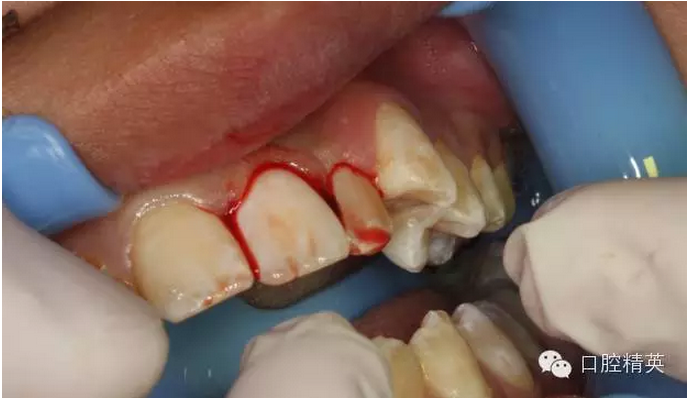

圖15.縫合初固定21

圖16.縫合初固定完畢